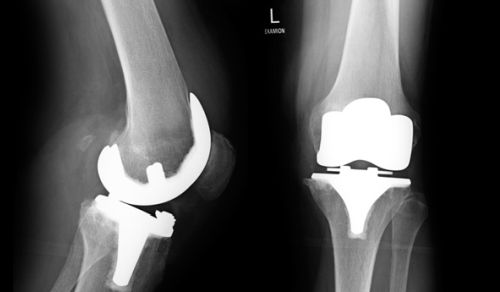

Typische Brüche treten auf am Wirbelkörper, in Hüftgelenksnähe, am Oberschenkel aber auch an Oberarmen und Handgelenken. Das tückische ist der Kreislauf, in dem sich die Patienten häufig befinden. Durch fortschreitende Immobilität nach einem Bruch wird die Bewegungsfähigkeit weiter eingeschränkt. Weitere Brüche sind fast schon vorprogrammiert. Um Osteoporose zu diagnostizieren, wird eine Knochendichtemessung durchgeführt.